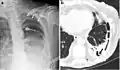

Chest X-ray showing bilateral fibrosis and pleural thickening in infection with non-tuberculosis mycobacteria.